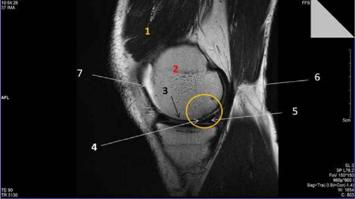

AusstellungMini-Magnet-Resonanz Experimente und Meniskus-Schaden in MR-BildernThema: Gesundheit TechnikBei dieser Doppelstation wird ein kleines Magnetresonanz (MR) Tischgerät gezeigt, mit dem einfache Versuche zur Erläuterung des Funktionsprinzips eines MR-Tomographen demonstriert werden. Ein Bildschirm zeigt MR-Schnittbilder eines menschlichen Knies mit Gewebetypen inkl. einem Meniskusschaden.Medizinische Forschungsmeile17:00 - 23:00 -